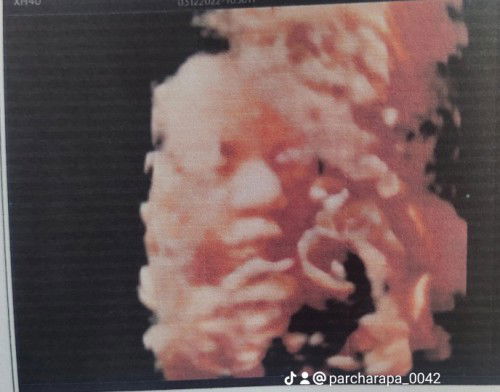

มาอวดลูกชายค่ะ 25w น้ำหนัก680g กำหนดคลอด17กุมภาพันธ์

มีแม่ๆคนไหนคลอดเดือนกุมภาพันธ์เหมือนกันบางมั้ยค่ะมาอวดรูปลูกเลยค่ะ❤👶